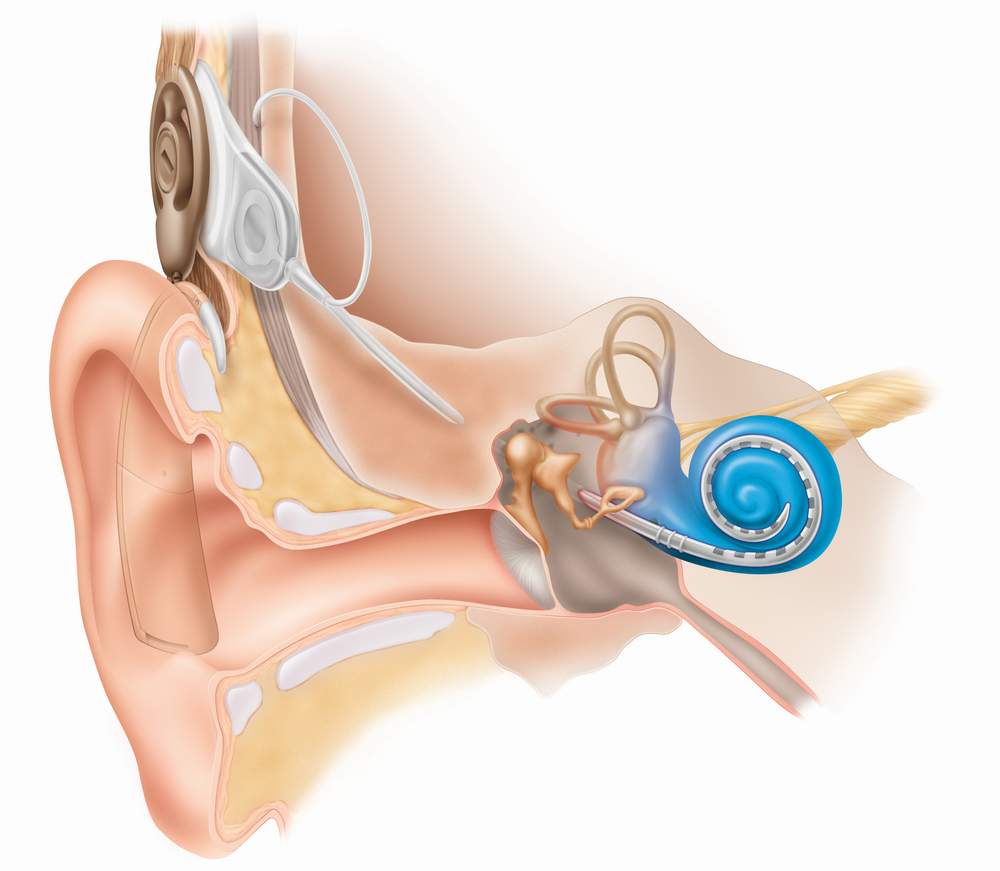

Also called as Otolaryngology is a branch of medicine which deals with medical and surgical management and treatment of patients with diseases and disorders of the ear, nose, throat (ENT), and related structures of the head and neck.The Best Possible Care To The Patients With Ailments Related To Ear, Nose & Throat, Of All Age Groups.The Department Is Dedicated To Expanding The Frontiers Of Diagnosis, Treatment And Research Of Disorders Of The Ear, Nose And Sinuses , Throat And The Anterior Skull Base.